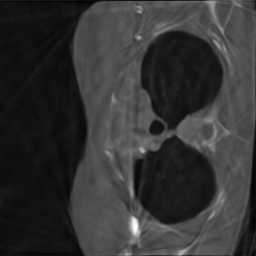

In our experiments, we consider a subsampling ratio of and , meaning that or respectively. The parameter encodes all the parameters above. The sensitivity maps and the trajectory perturbations are usually unknown, making MRI reconstruction a blind inverse problem. Examples of realistic sampling trajectories used in this work are displayed in Fig. 2, bottom.

Following [36], we generate random target densities as anisotropic power decaying distributions. They are parameterized by a random vector that encodes the density at origin, the anisotropy and the power decay law. To avoid solving (13) at training time, we have pre-computed sampling patterns. The corresponding vectors have been generated by using a max-min sampling (see [72, 25]) of a set of an admissible set of parameters . We refer to [36] for more details. Examples of densities and sampling patterns without constraints are displayed in Fig. 2(a)-2(e). Notice that we did not include trajectory constraints for generating this figure. They are taken into account for the blind inverse problem part.